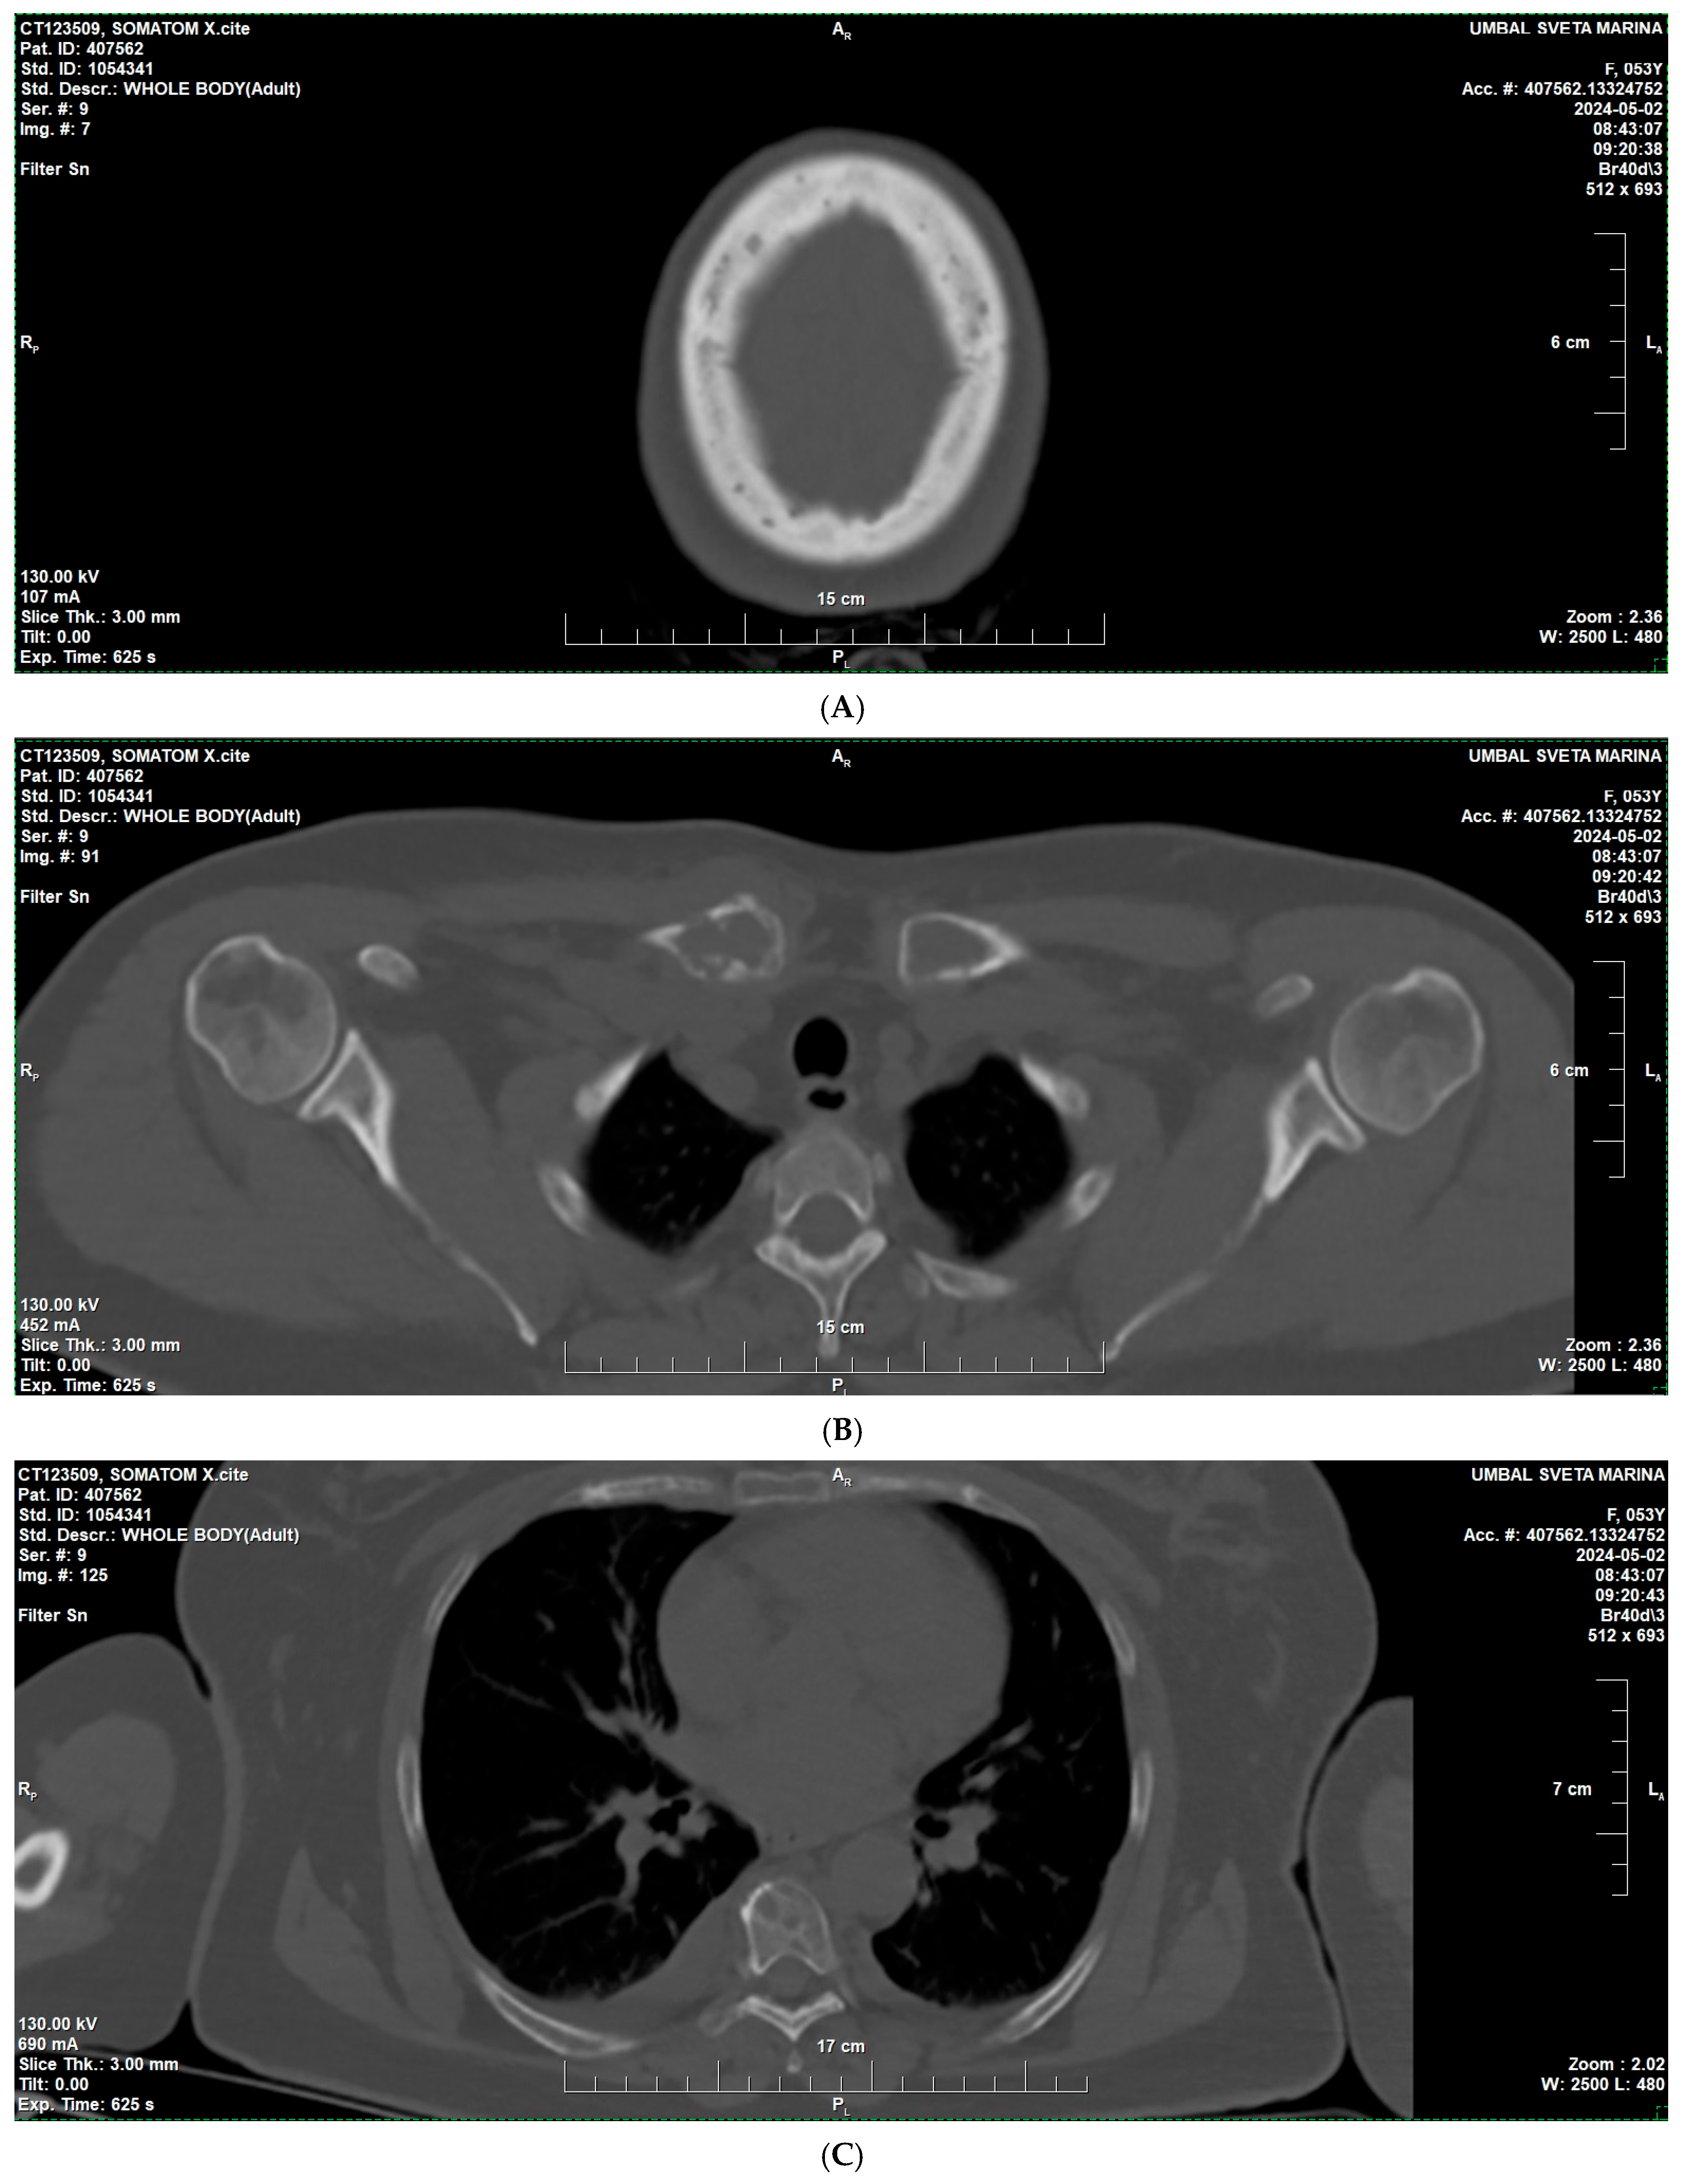

2. Case Presentation